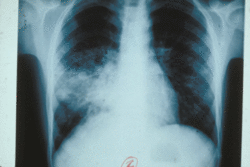

AccueilActualitéScienceBPCO : pourra-t-on bientôt changer le cours de la maladie ?BPCO : pourra-t-on bientôt changer le cours de la maladie ? Publié le : 16/11/2015 Temps de lecture : 3 min Actualité, ScienceVous lisez une page qui n’a pas été modifiée depuis 2015.Des chercheurs de l’Inserm travaillent au développement d’un médicament qui pourrait enfin permettre d’éviter l’inéluctable aggravation de la bronchopneumopathie chronique obstructive. En identifiant un mécanisme associé aux exacerbations de cette maladie chronique inflammatoire des bronches, les chercheurs ont en effet découvert une cible thérapeutique directement exploitable.Voilà une piste thérapeutique qui pourrait « révolutionner » la prise en charge de la bronchopneumopathie chronique obstructive (ou BPCO). Le Pr Patrick Berger* n’y va pas par quatre chemins pour qualifier le potentiel de la découverte que vient de réaliser de son équipe au CHU de Bordeaux. Actuellement, cette maladie chronique des bronches ne peut être guérie. Les traitements disponibles sont symptomatiques, ne soulageant que transitoirement les patients, avec une efficacité modérée. Pourtant, la BPCO est une maladie extrêmement répandue dont le principal facteur de risque est le tabac. « En France, 75% des adultes sont des fumeurs ou des ex-fumeurs. Parmi eux, la moitié des individus présentent une BPCO même s’ils l’ignorent encore. D’ici 2030, il s’agira de la quatrième cause de mortalité dans le monde », détaille Patrick Berger. C’est dire si l’enjeu est de la taille. Étudier les exacerbationsLa BPCO est caractérisée par une inflammation des bronches et un remodelage de celles-ci. Elle entraine une obstruction progressive des voies aériennes et des difficultés à respirer. Des exacerbations, c’est à dire une aggravation brutale des symptômes, surviennent chez 80% patients et aboutissent souvent à une hospitalisation et un sur-risque de mortalité dans les mois et les années qui suivent. C’est ce problème que les chercheurs ont voulu cibler. Dans deux autres maladies respiratoires, l’asthme et la fibrose pulmonaire, il existe une élévation de la concentration en fibrocytes, des cellules souches de la moelle osseuse qui passent dans le sang et viennent coloniser les régions inflammées, contribuant à l’aggravation de ces maladies. Dans le cas de l’asthme, ces cellules se différencient en cellules musculaires lisses (myocytes) qui accroissent les contractions des bronches. En cas de fibrose pulmonaires, les fibrocytes se différencient en fibroblastes (des cellules de soutien des tissus) et accentuent la fibrose. Les chercheurs se sont donc demandé si des fibrocytes n’étaient également impliqués dans les exacerbations de BPCO, contribuant à leur sévérité. Des fibrocytes atypiques à cibler© Inserm, L. Guillevin La pneumonie est une inflammation des poumons habituellement causée le plus souvent par un virus ou une bactérie. Pour en avoir le cœur net, ils ont analysé la concentration des fibrocytes circulant dans le sang de 65 patients concernés par une exacerbation bronchique, et suivi leurs capacités respiratoires pendant au moins deux mois. Ils ont procédé de même chez des individus montrant une BPCO stable sans exacerbation, ainsi que chez des sujets non atteints de BPCO. C’est ainsi qu’ils ont constaté une augmentation massive de la concentration en fibrocytes au cours des exacerbations associées à la BPCO. En fait, « plus la concentration en fibrocytes est élevée, plus le pronostic du patient est mauvais, constituant même un indice de mortalité à trois ans. En outre, plus la concentration des fibrocytes reste élevée dans les deux mois qui suivent l’épisode, plus le souffle est altéré », résume Patrick Berger. En regardant de plus près ces fibrocytes, les auteurs ont constaté qu’ils portaient deux récepteurs spécifiques à certaines chimiokines, des substances produites par l’organisme capables d’attirer les cellules dans le sang. « Ces fibrocytes semblent présenter une hypersensibilité à deux chimiokines qui provoquerait leur migration jusque dans les bronches au moment de l’exacerbation », explique le chercheur. Les mécanismes de cette migration sont à l’étude. Les auteurs tentent en outre de savoir si, une fois arrivés dans les bronches, ces cellules se différencient en myofibroblastes pour contribuer au remodelage des bronches et à l’aggravation de la maladie. Un médicament à l’essaiEn attendant de clarifier ces points, l’association entre la migration des fibrocytes dans le sang des patients atteints de BPCO et le pronostic de leur maladie est suffisamment claire pour tenter d’enrayer ce phénomène. Les auteurs ont testé une molécule déjà sur le marché dans le cadre d’une indication hématologique (le plerixafor). Elle agit en bloquant un des récepteurs à chimiokines identifié à la surface des fibrocytes (CXCR4). Les résultats obtenus in vitro sont prometteurs et ont conduit les chercheurs à déposer un brevet pour protéger ces travaux. Un premier essai clinique pourrait prochainement démarrer. « Bloquer cette migration pourrait en effet, pour la première fois, changer l’histoire de la maladie », conclut le chercheur. Note*unité 1045 Inserm/Université de Bordeaux, Centre de recherche Cardio-thoracique de Bordeaux SourceI. Dupin et coll. Journal of Allergy and Clinical Immunology, édition en ligne du 23 octobre 2015